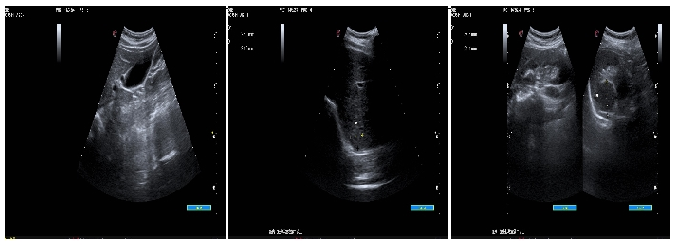

09、**女士,56岁

于2023年7月25日在银川仁泰体检部体检,腹部彩超检查提示:左侧肾上腺区可见一低回声团,大小约37x34mm,边界欠清,内回声不均。考虑:左侧肾上腺区占位性病变(性质待定)。建议客户到综合医院专科进一步检查。2023年8月2日跟踪回访,已在当地某三甲医院住院,准备手术。